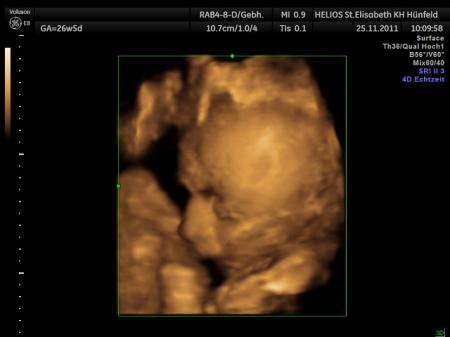

Sooo unser kleiner Prinz ist kerngesund... CTG war auch super Wehentätigkeit liegt so bei 16-21 ;) Und der Prinz ist jetzt stolze 2046g schwer und ist 46cm groß!!! :) Ich wünsche Euch allen noch einen schönen Tag!!!! ;)

Bild zu